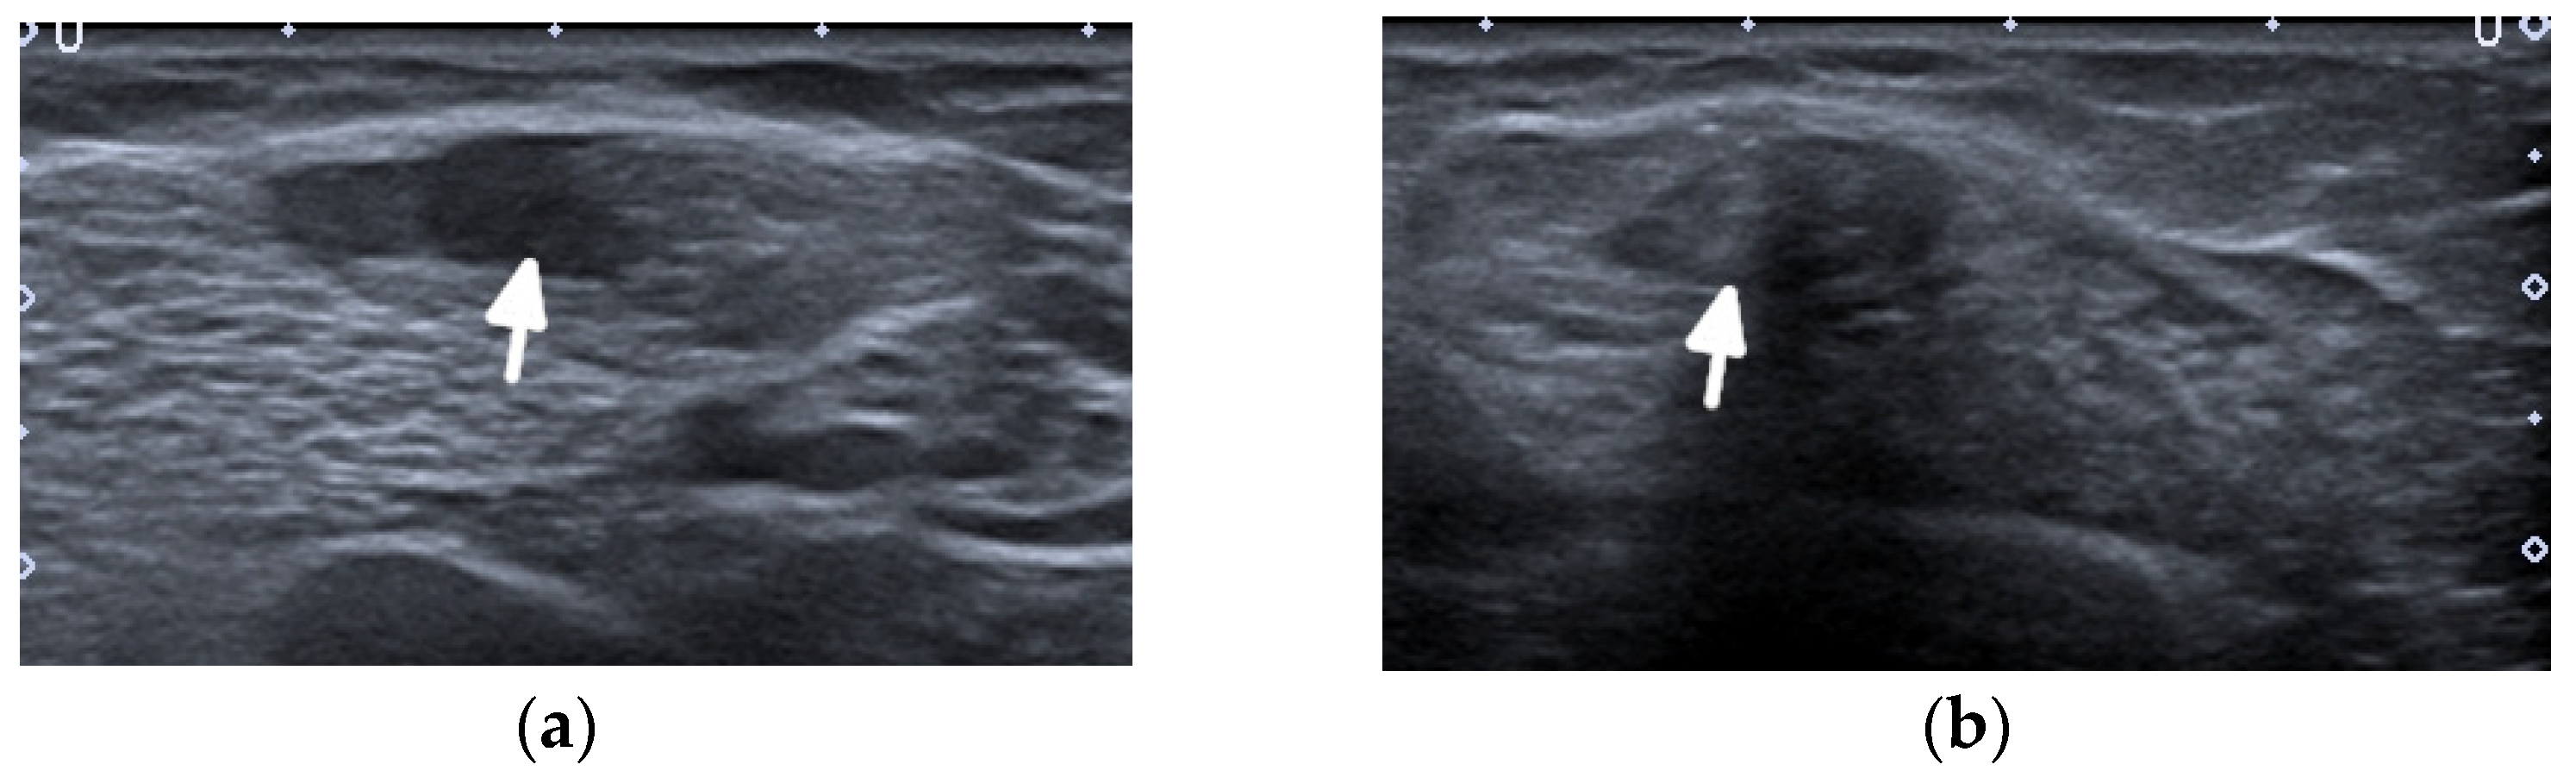

Typical for SLE are spontaneous tendon ruptures (Figure 6, Figure 7 and Figure 8), most commonly of the patellar and Achilles tendons. In SLE, inflammatory changes as well as tears may be observed not only on the background of tenosynovitis, but also involving the tendon in the absence of tenosynovitis, even along the intramuscular segment [10] (Figure 8).

Figure 6.

A complete spontaneous tear of the right posterior tibialis tendon (PTT) 2 cm above the medial malleolus in a 46-year-old female with systemic lupus erythematosus. (a,b) short-axis gray-scale ultrasound (US) images of the medial aspect of the bilateral ankles show the normal echogenic fibrillar appearance of the healthy left PTT (a, arrow) compared to an enlarged, torn right hypoechoic PTT in the same region between calipers in (b). (c) Short-axis power Doppler US image of the affected right side shows hyperemia in the PTT tendon stump, with additional hyperemia in the tendon sheath consistent with tendinopathy and tenosynovitis. Two tiny red dots at the periphery of green Doppler box represent normal vessels.

Figure 7.

A complete tear of the proximal part of the bare tendon of the distal biceps brachii bilaterally in the same patient as in Figure 6. Short-axis (a,b) and long-axis (c,d) gray-scale ultrasound images of the bilateral elbow/distal arms show rupturing of the bilateral distal biceps tendons at the level of the myotendinous junction with hypoechoic proximal stums consistent with tendinopathy (arrows). In (c,d), note the retracted bilateral biceps muscles.